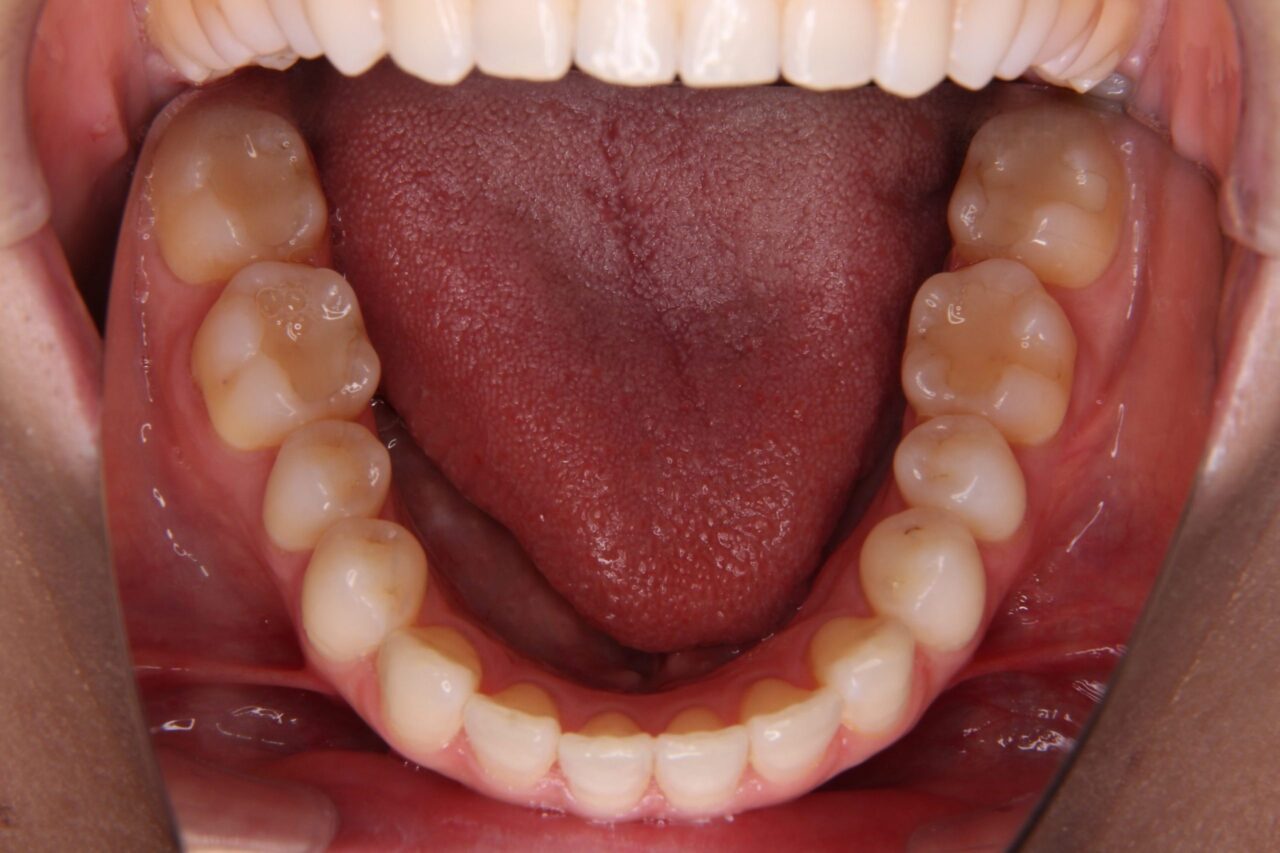

矯正後の歯列

矯正後の歯列がこちらです↓↓↓